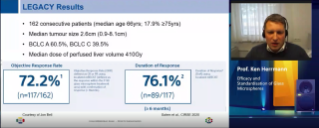

EANM 2022 - Y-90 Glass Microspheres, Personalised Dosimetry, Gudelines and Clinical Data

Oct 16, 2022

External Link( 92.0 KB )

A panel of international experts share the latest TARE clinical evidence through cases and discussions and review how this translate into the guidelines for both primary and secondary liver cancer.

Moderator: Prof. Ken Herrmann -

Optimizing SIRT planning for superior patient outcomes

Sep 13, 2020

External Link( 12.0 KB )

Prof. Eric Vibert introduces the symposium

Optimizing SIRT planning for superior patient outcomes

Sep 13, 2020

External Link( 12.0 KB )

Personalised dosimetry: unique to glass microspheres. Dr Yan Rolland

Optimizing SIRT planning for superior patient outcomes

Sep 13, 2020

External Link( 16.0 KB )

Case examples of personalised dosimetry in curative and palliative scenarios. Dr Rafael Duran.

Optimizing SIRT planning for superior patient outcomes. Discussion and Q&A

Sep 13, 2020

External Link( 15.0 KB )

Panelists discussion

Optimizing SIRT planning for superior patient outcomes. Refine your SIRT Planning

Sep 13, 2020

External Link( 16.0 KB )

Prof. Marnix Lam